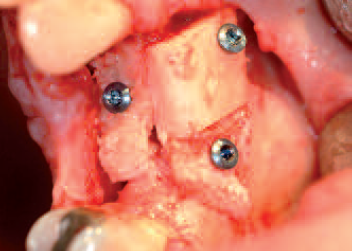

Bone

grafts fixed with micro-screws

Augmented material fully covered by the collagen membrane

Collagen membrane positioned above the defect before wound closure